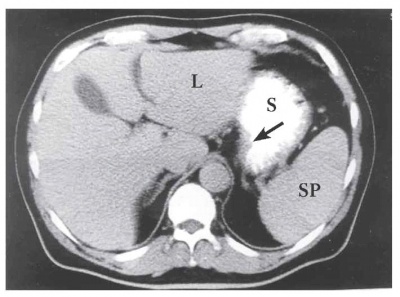

טומוגרפיה ממוחשבת - מאפשרת להדגים את גודל השאת, התפשטותה לאיברים סמוכים, בלוטות לימפה מוגדלות או גרורות לאיברים אחרים (תצלומים 21.3-18.3). ב-CT הדיוק באבחנת T4 הוא 90% וב-T1 הוא 23%.